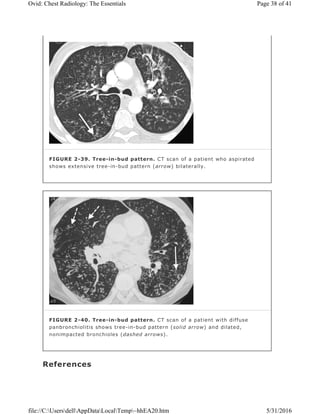

FIGURE 2-39. Tree-in-bud pattern. CT scan of a patient who aspirated

shows extensive tree-in-bud pattern (arrow) bilaterally.

FIGURE 2-40. Tree-in-bud pattern. CT scan of a patient with diffuse

panbronchiolitis shows tree-in-bud pattern (solid arrow) and dilated,

nonimpacted bronchioles (dashed arrows).